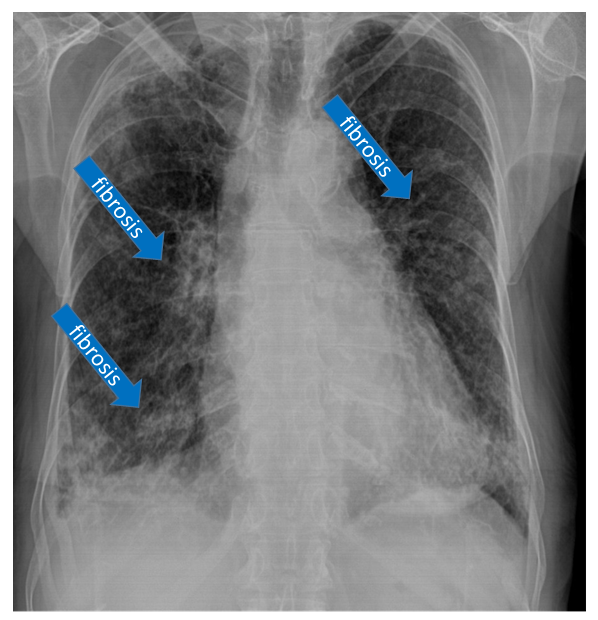

Lung Fibrosis

Airway remodeling is a prominent feature of asthma and chronic obstructive pulmonary disease. The extent of remodeling is correlated with the severity of both diseases. A major contributor to airway remodeling is a process called fibrosis, or scar tissue formation, which causes a thickening and stiffening of the airways. Ultimately, fibrosis leads to an increase in the effort required for breathing and the need for supplemental oxygen.

Fibrosis is caused by interaction of several types of lung cells that produce an overabundance of fibrous proteins, including collagen, leading to reduced lung elasticity. Normally, there is a balance between the synthesis and breakdown of these proteins that are important for providing the structural and supportive framework of the airways and blood vessels in the lungs.